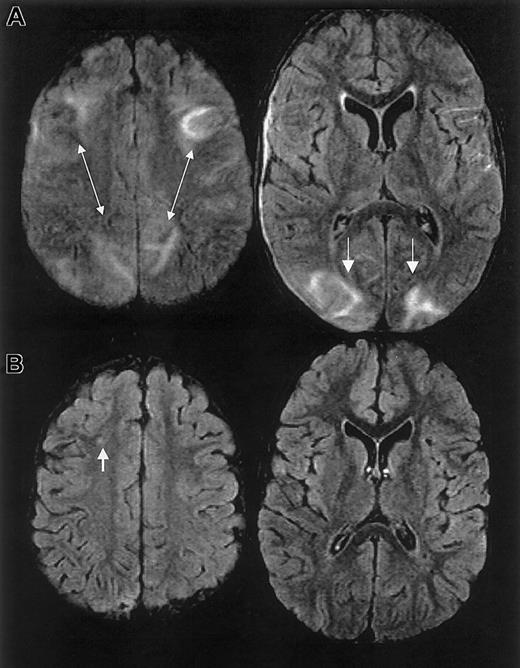

One year prior to ACS episode, the patient had normal MRI/MRA and transcranial Doppler studies. MRI on day 10 and 1 month following discharge revealed RPLS with superimposed ischemic white matter changes (Figure 2).

MRI findings for case 2.

Multifocal areas of signal hyperintensity predominantly limited to the cortex of the posterior parietal and occipital lobes on FLAIR T2-weighted images, including punctate areas of abnormality in the deep, periventricular white matter of the right frontal lobe and of the cortex of the right medial parietal lobe. MRI done 1 month following discharge revealed punctate lesions in the frontal lobe, representing subacute to chronic ischemic changes, but resolution of the T2 hyperintense lesions in the posterior distribution.